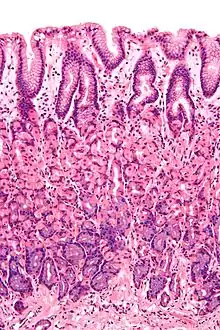

Tværsnit af tarmens slimhinde.

En slimhinde er en biologisk membran, der beklæder de forskellige hulrum i kroppen og dækker overfladerne på de indre organer. Slimhinder har forskellige opbygninger afhængig af funktion men består generelt af et eller flere lag af epitelceller på lag af bindevæv. De er af endodermisk oprindelse og findes i et kontinuum med huden ved de forskellige kropsåbninger, som ved øjet, øret, indersiden af næsen, indersiden af munden, læber, vagina, urinrør samt anus. Nogle slimhinder udskiller slim, en tyk beskyttende væske. Slimhindens funktion er at stoppe patogener og skidt fra at komme inde i kroppen og forhindre dehydrering af kroppens væv.